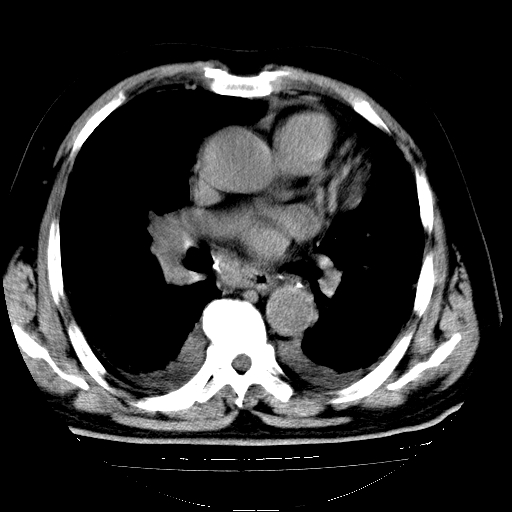

男,68岁,咳嗽、胸闷、发烧三天,查体:双肺散在湿罗音。

4.肺原性心脏病;

5.双侧胸腔少量积液;双侧胸膜增厚。

慢支合并感染.间质纤维化,心衰双侧少量胸腔积液

慢性支气管炎伴感染、肺气肿;间质性病变;双侧胸腔积液。

支持 慢支合并感染.间质纤维化,心衰双侧少量胸腔积液.

两肺广泛条索状、网格状、蜂窝状改变。肺间质纤维化,肺心病,双侧胸腔积液